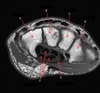

What is letter A?

ACETABULUM

94

What is letter B?

LABRUM

95

What is letter C?

FEMORAL NECK

96

What is letter D?

OBTURATOR EXTERNUS

97

What is letter E?

ADDUCTOR MUSCLES

98

What is letter F?

VASTUS LATERALIS

99

What is letter G?

FEMUR

100

What is letter H?

GREATER TROCHANTER

101

What is letter J?

FEMORAL HEAD

102

What is letter K?

BODY OF ILIUM

103

What is letter L?

ILIAC CREST

104

BLADDER

105

106

LT FEMORAL HEAD

107

ISCHIUM

108

RT FEMORAL HEAD

109

SUPERIOR PUBIC RAMUS

110